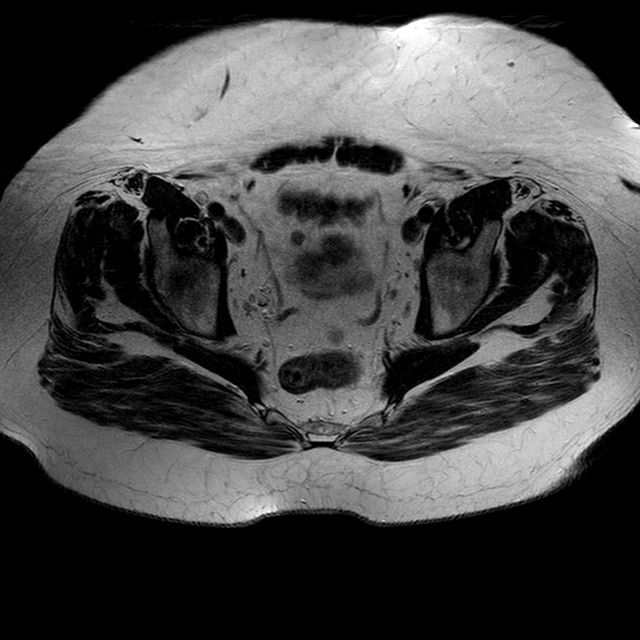

Esami: RMN BACINO

T2w TSE

Evidenti e simmetriche alterazioni osteofitosiche in regione coxo femorale con riduzione delle rime articolari. Degenerazione completa del cercine glenoideo. Non attuali segni di versamento articolare. Non segni di edema osseo che escludono attuale algodistrofia od osteonecrosi. Lieve e simmetrica riduzione del trofismo della muscolatura glutea.